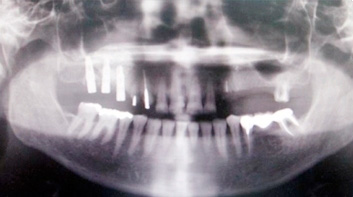

Клинический случай 2. Синус-лифтинг с имплантацией (имплантаты «Юник» и «Перфект»)

1) Панорамная рентгенограмма больной с частичной адентией на верхней челюсти слева. Планируется удаление корней 23 и 27 зубов и установка 5 имплантатов в области зубов с 23 по 27. В области зубов 25, 26 и 27 будет проведена направленная регенерация костной ткани «синус лифтинг» с одномоментной установкой имплантатов.